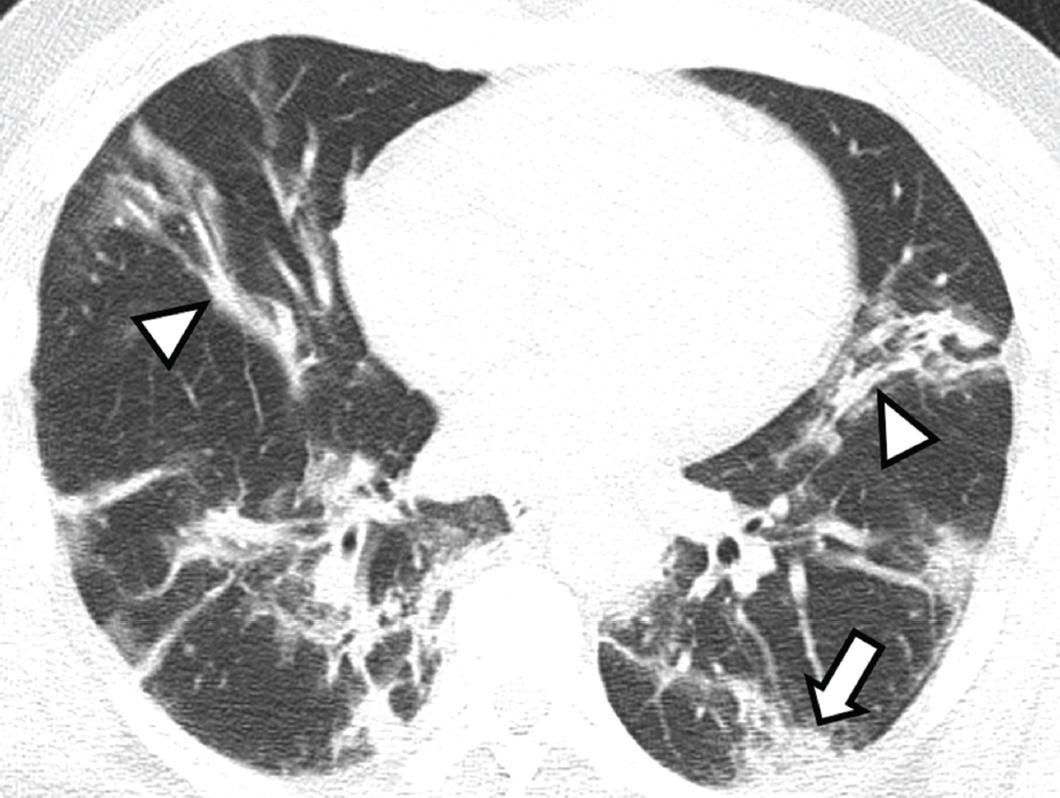

Figura 5 Hombre con neumonía causada por SARS-CoV-2 de 10 días de evolución, quien se encuentra en una etapa máxima de la enfermedad. Se observan bandas subpleurales (cabeza de flecha) asociadas a consolidaciones densas (flecha).

– Etapa máxima (de nueve a 13 días después del síntoma inicial), en la que se encontraron 19 pacientes. Se observaron los patrones de vidrio esmerilado, consolidación y empedrado en 79, 68 y 26 %, respectivamente. Las bandas subpleurales leves, moderadas y severas estuvieron presentes en 47, 26 y 5 %, respectivamente.

–Etapa máxima: el hallazgo más frecuente fue la consolidación densa. En nuestra investigación, los hallazgos incluyeron patrones de vidrio esmerilado, consolidación y empedrado, así como bandas parenquimatosas que causan distorsión de la arquitectura (Figura 5).